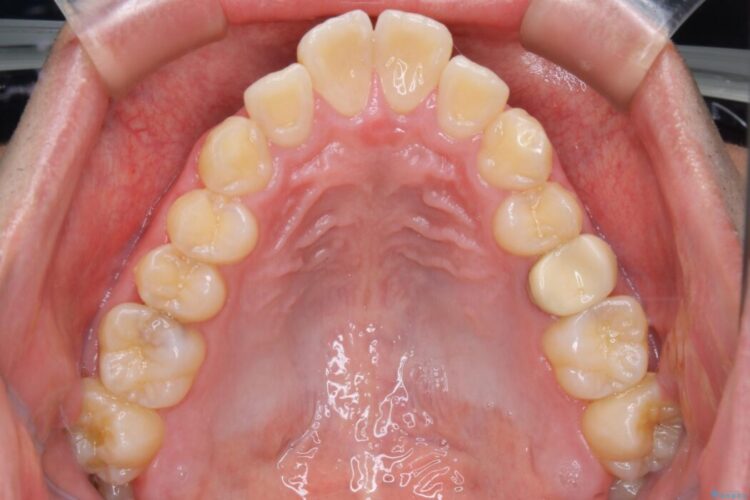

上の歯の出っ歯と下の歯のガタつきが気になるとご来院された患者様です。

出っ歯とガタつきの改善には抜歯が必要と診断し、上下左右第一小臼歯を抜歯することとしました。